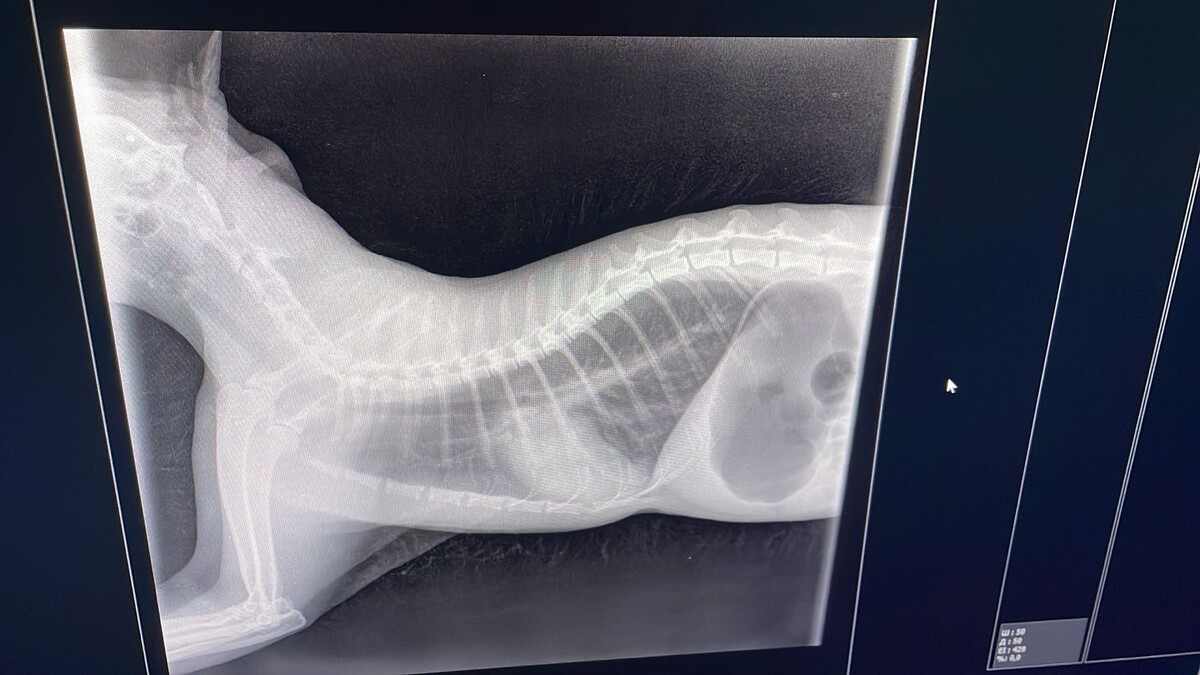

Осмотрев, сделать рентген мы пришли в ужас, у него в легких пошел воспалительный процесс. Большинство внутренних органов были воспалены, после уколов и нескольких часов в кислородной камере его переместили в стационар. Первые несколько дней, за ним следили чуть-ли не каждые 10 минут, т.к. он дышал только ртом.

первый снимок 03.01.25

Снимок 05.01.25